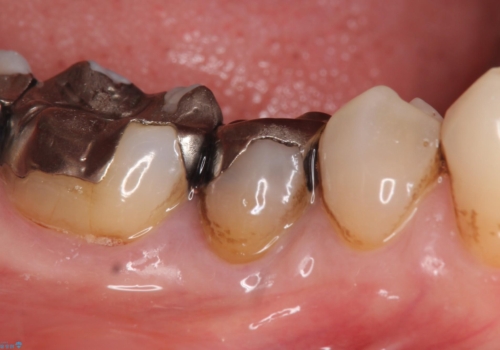

- 右下の歯でものを咬むと違和感があるので診て欲しいといらっしゃった方の症例です。

右下5番目の歯に根尖病変を認めたため、再根管治療を行い、オールセラミッククラウンによる補綴を行いました。